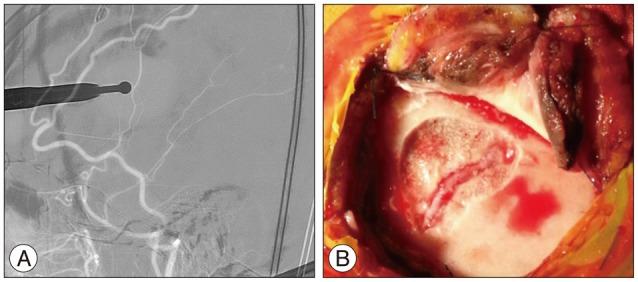

A 66-year-old woman presented with intermittent paraparesis and generalized tonic-clonic seizure. Cerebral angiography demonstrated dural arteriovenous fistula (AVF) involving superior sagittal sinus (SSS), which was associated with SSS occlusion on the posterior one third. The dural AVF was fed by bilateral middle meningeal arteries (MMAs), superficial temporal arteries (STAs) and occipital arteries with marked retrograde cortical venous reflux. Transfemoral arterial Onyx embolization was performed through right MMA and STA, but it was not successful, which resulted in partial obliteration of dural AVF because of tortuous MMA preventing the microcatheter from reaching the fistula closely enough. Second procedure was performed through left MMA accessed by direct MMA puncture following small decortications of cranium overlying the MMA using diamond drill one week later. Microcatheter could be located far distally to the fistula through 5 F sheath placed into the MMA and complete obliteration of dural AVF was achieved using 3.9 cc of Onyx.

一名66岁女性出现间歇性双下肢轻瘫和全身性强直阵挛发作。脑血管造影显示硬脑膜动静脉瘘(AVF)累及上矢状窦(SSS),且与后三分之一的上矢状窦闭塞有关。该硬脑膜AVF由双侧脑膜中动脉(MMA)、颞浅动脉(STA)和枕动脉供血,伴有明显的皮质静脉逆行回流。通过右侧MMA和STA进行了经股动脉Onyx栓塞,但未成功,由于MMA迂曲,微导管无法足够接近瘘口,导致硬脑膜AVF部分闭塞。一周后,使用金刚石钻头在覆盖MMA的颅骨上进行小范围去骨皮质后,通过直接穿刺MMA进入左侧MMA进行了第二次手术。通过置于MMA的5F鞘管,微导管能够置于瘘口远端,使用3.9 cc Onyx实现了硬脑膜AVF的完全闭塞。